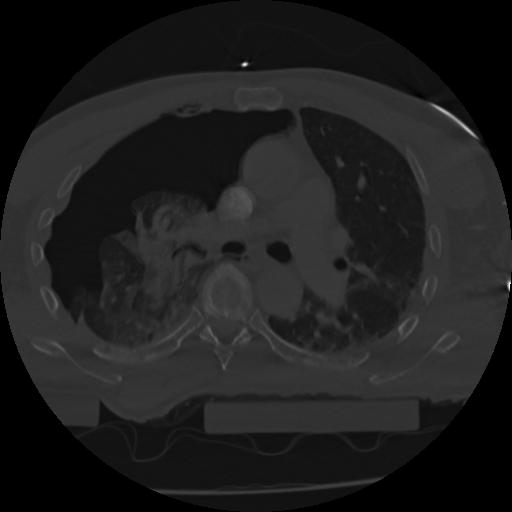

22 ANGIO,CE,Vol,0.5,ANGIO,,